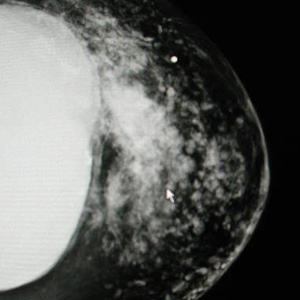

Another Example Of MRI Information.

This MRI Shows Deep Wrinkles or Invaginations Of The Shell. This Is Evidence Of An Old Under-Filled Silicone Implant.

This Is Different From The Linguini Sign Shown Above.

Although The Implants Were Not Ruptured, Old Implants Can Have Gel Can "Bleed" Through The Implant Shell Allowing The Body To Have Direct Conatct With The Gel

Left MRI